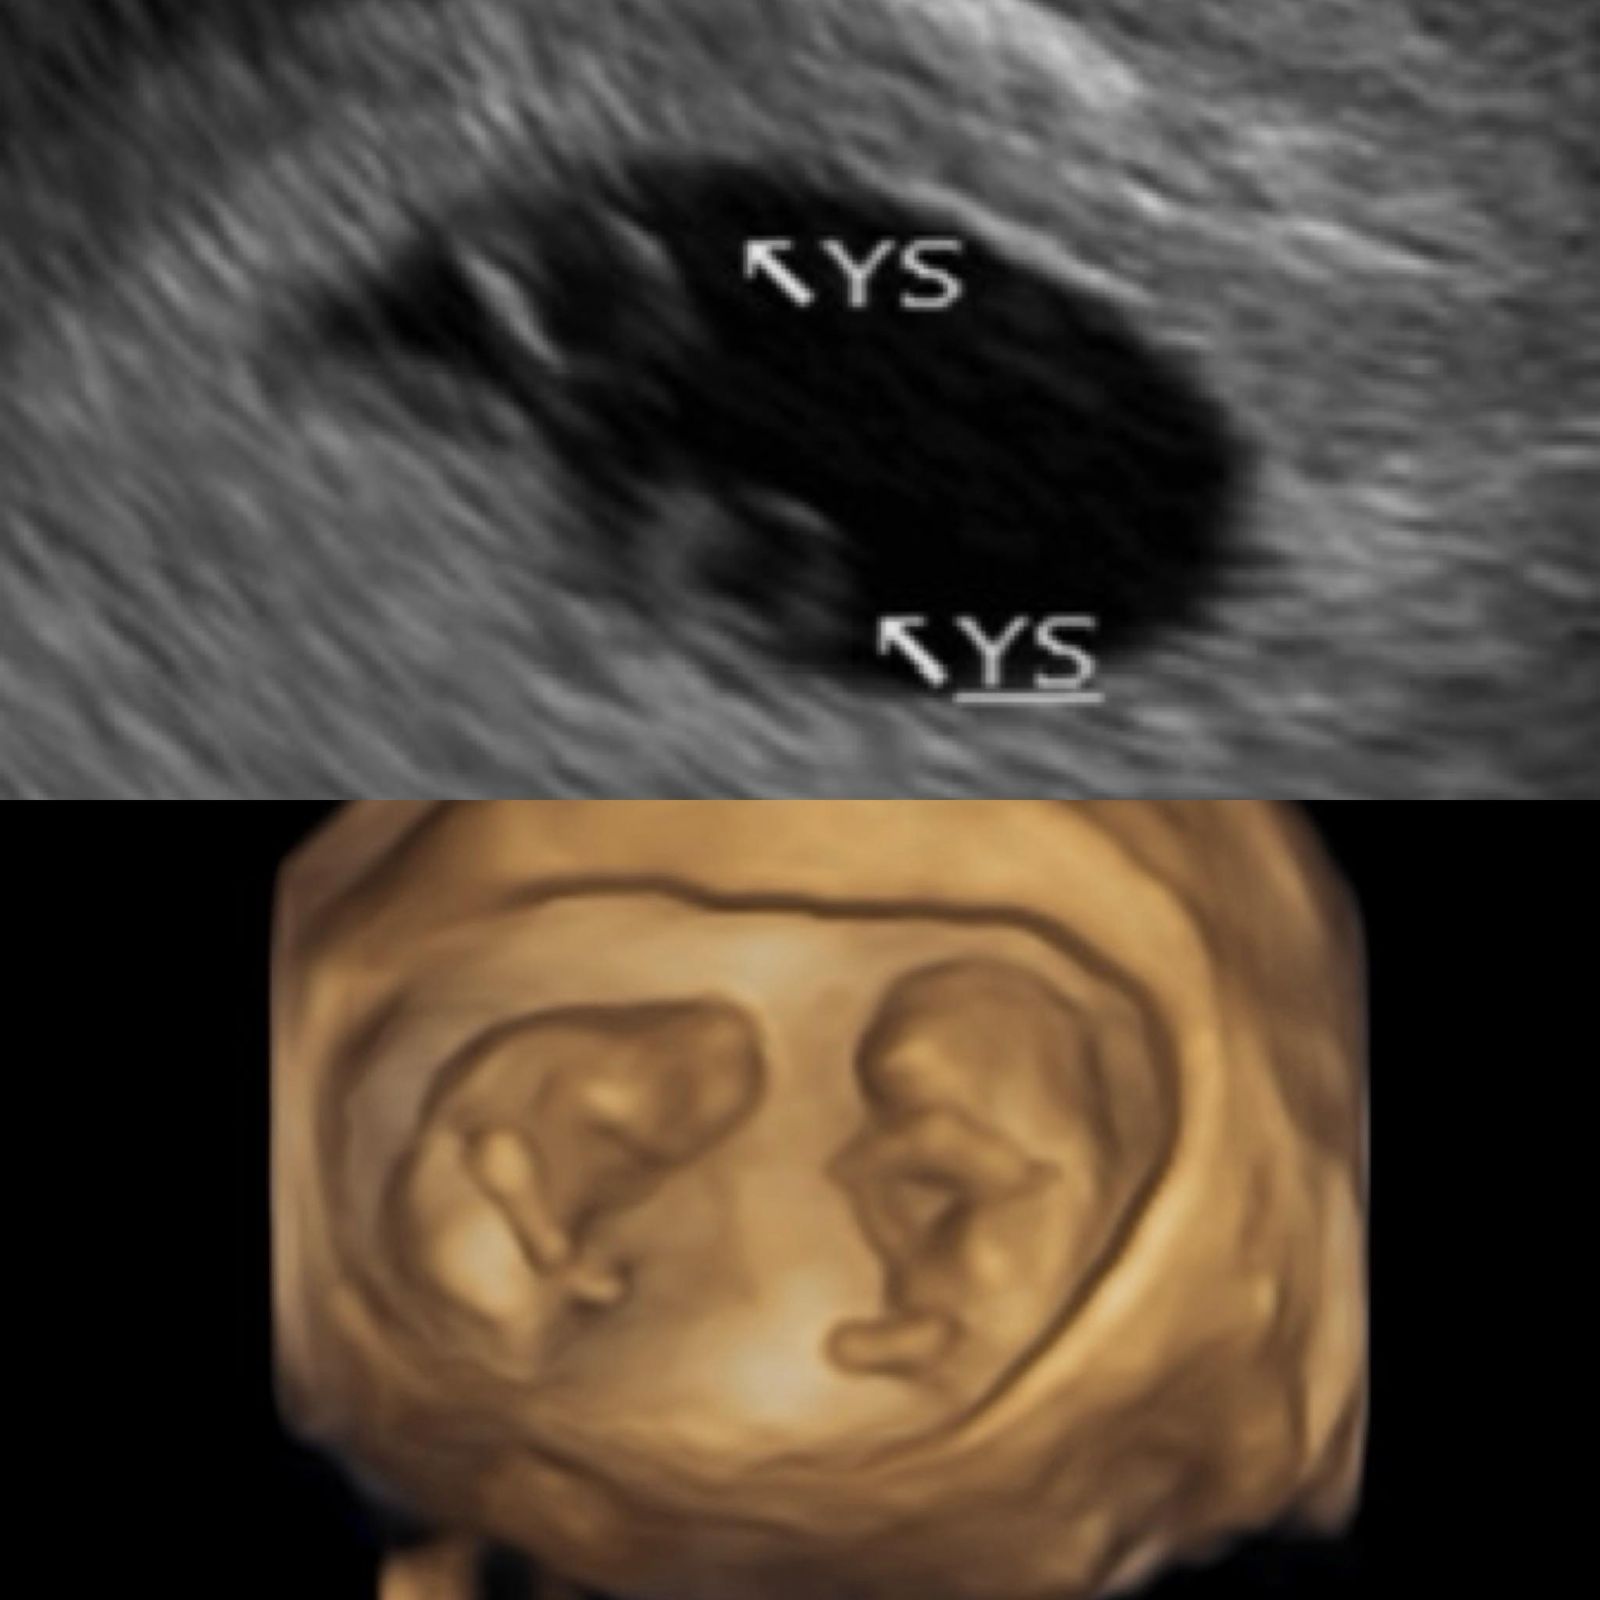

鄭家純在臉書發文透露,今年1月上旬不幸小產後,原本聽從醫師建議準備休養3個月再規劃懷孕,甚至已與茂盛醫院預約年後進行胚胎植入。沒想到在排卵期避孕的情況下,生理期卻遲遲未報到,直到除夕當天驗出淡淡的兩條線,驚覺小產後月經還沒來就又懷孕了。更讓她意外的是,回台產檢時,超音波影像中竟出現兩個卵黃囊在同一個胎囊裡,讓超音波師也興奮恭喜她懷上雙胞胎。

鄭家純曬出超音波照宣布喜訊。翻攝鄭家純臉書